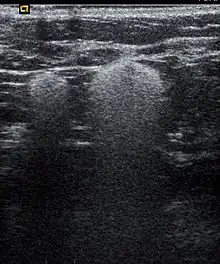

| Snowball like hyperechogenic axillary lymph nodes in a woman with silicone implants removed due to complications | |